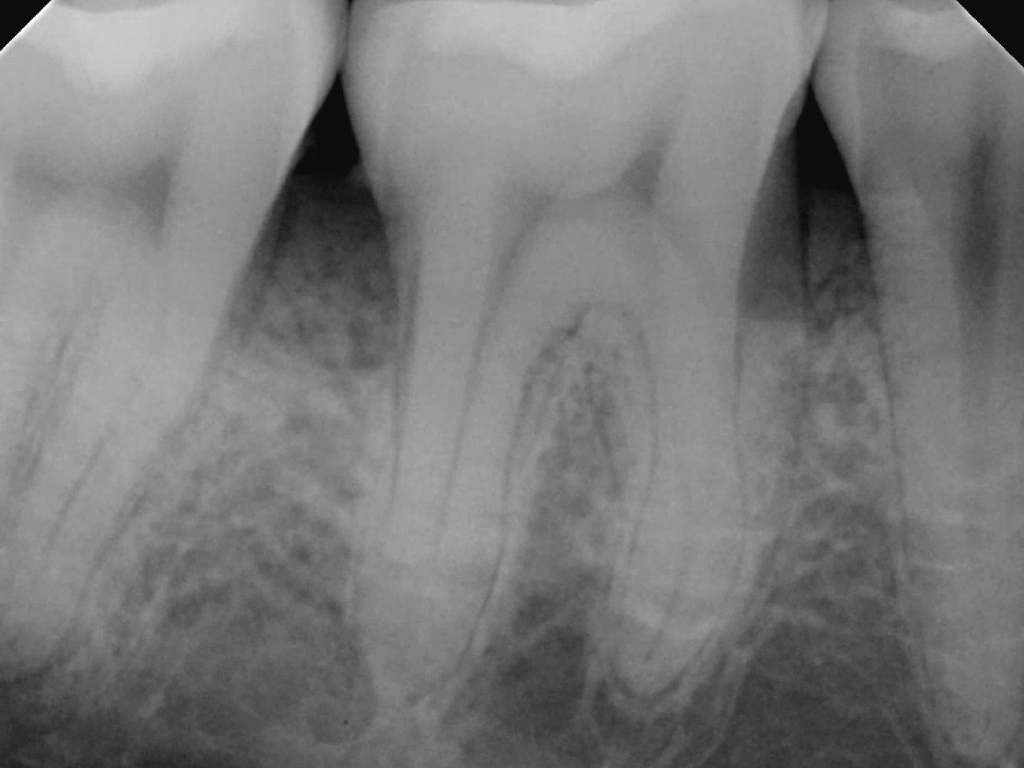

Fig 1. Inaccurate probing angle wrongly indicates probing depth at 3 mm, which does not correspond to the radiographic finding shown in Fig 2.

Fig 2. Periapical radiograph showing presence of distal bone loss and calculus.